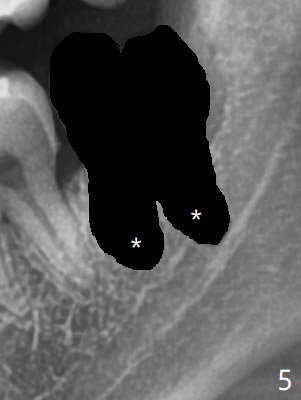

A 26-year-old man presents to clinic with pericoronitis at #17; the tooth #16 bites on the distal swollen gingiva of the tooth #17 (Fig.1). Since there appears to be no bone loss distal of #18, collagen plug, instead of Osteogen plug (Fig.2,3), will be placed in the socket(s) after extraction (Fig.4,5). For easy insertion, the plug is cut apically (Fig.6 *). The wound is closed with 4-0 plain gut suture. The patient returns for #1 and 32 extraction, eight months post #16 and 17 extraction. As usual, no bone substitute is placed in #1 socket after extraction (Fig.7). After #32 extraction, the distal socket looks large so that Augma (Bond Apatite) is placed and pressed (A), followed by a piece of Collagen Plug (C, to prevent Augma dissolved by saliva in case premature loss of suture). In fact there is also buccal defect at #32 due to chronic infection and heavy calculus. There is cortical bone formation at #16 socket opening (^). The mesial and distal sockets of #17 (*) seem to be obliterated because of placement of Collagen Plug. Return to Plug, Weichat Xin Wei, DDS, PhD, MS 1st edition 01/05/2019, last revision 09/22/2019